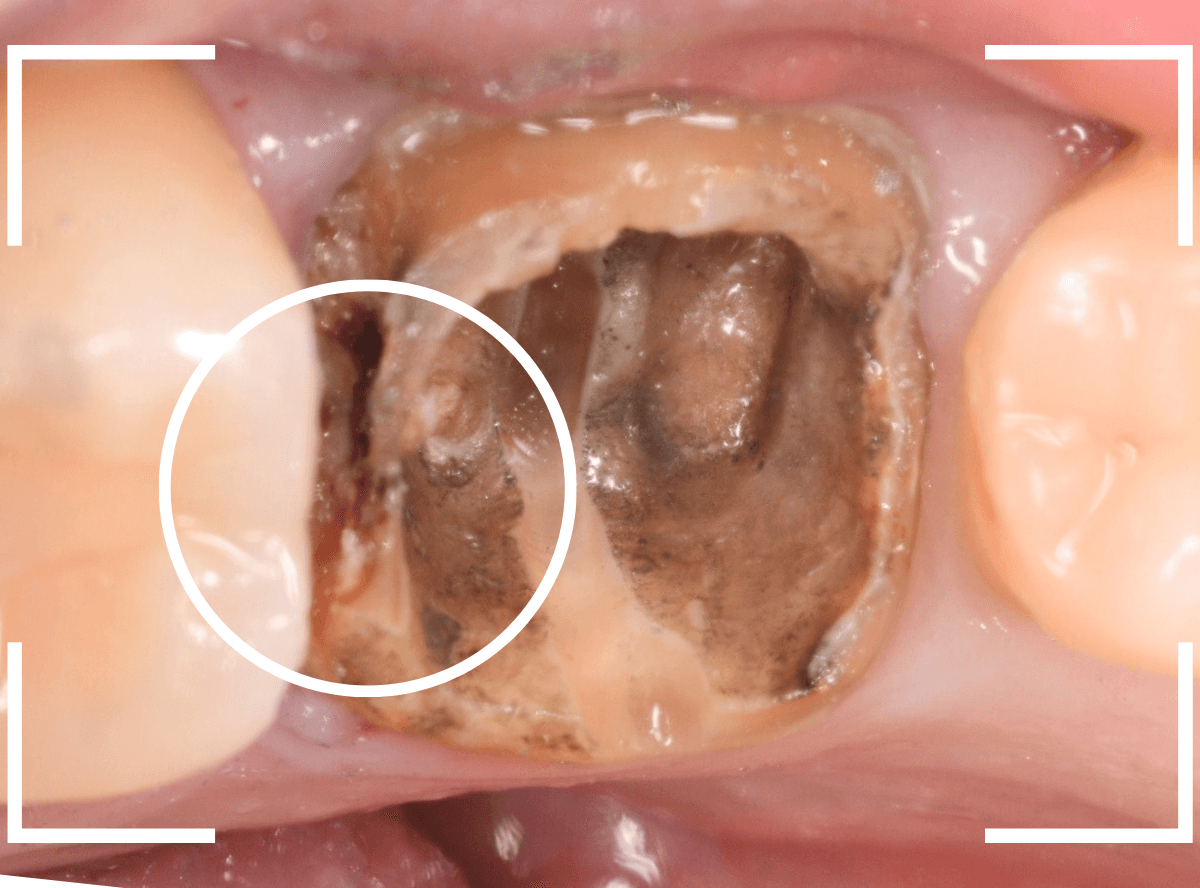

メタル・コアを除去して、明視野で虫歯を確認します。

幸い、浅い状態に入っていたメタル・コアでしたので比較的容易に除去する事ができました。

虫歯が歯肉の下まで進んでいるようですので、麻酔をして歯肉を少し除去しながら虫歯の処置をします。